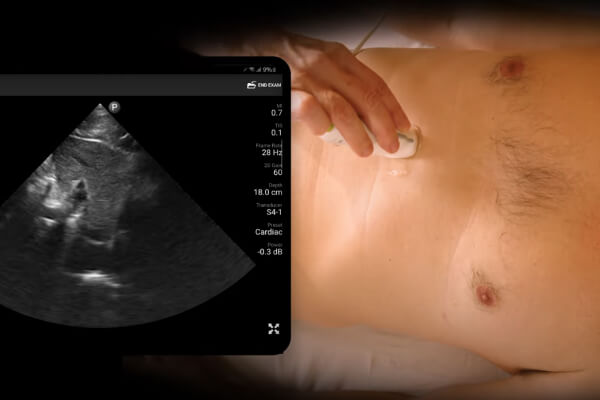

PSAX View

Learn how to obtain the parasternal short axis view